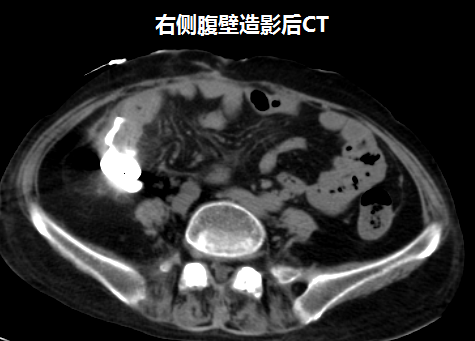

吴万庆副主任医师接诊后,详细了解病史及查体,经过造影及CT检查,确定瘘口的部位及腹腔脓腔情况,发现患者腹壁有三个瘘口,粪便外渗,诊断考虑为克罗恩病并发肠瘘。